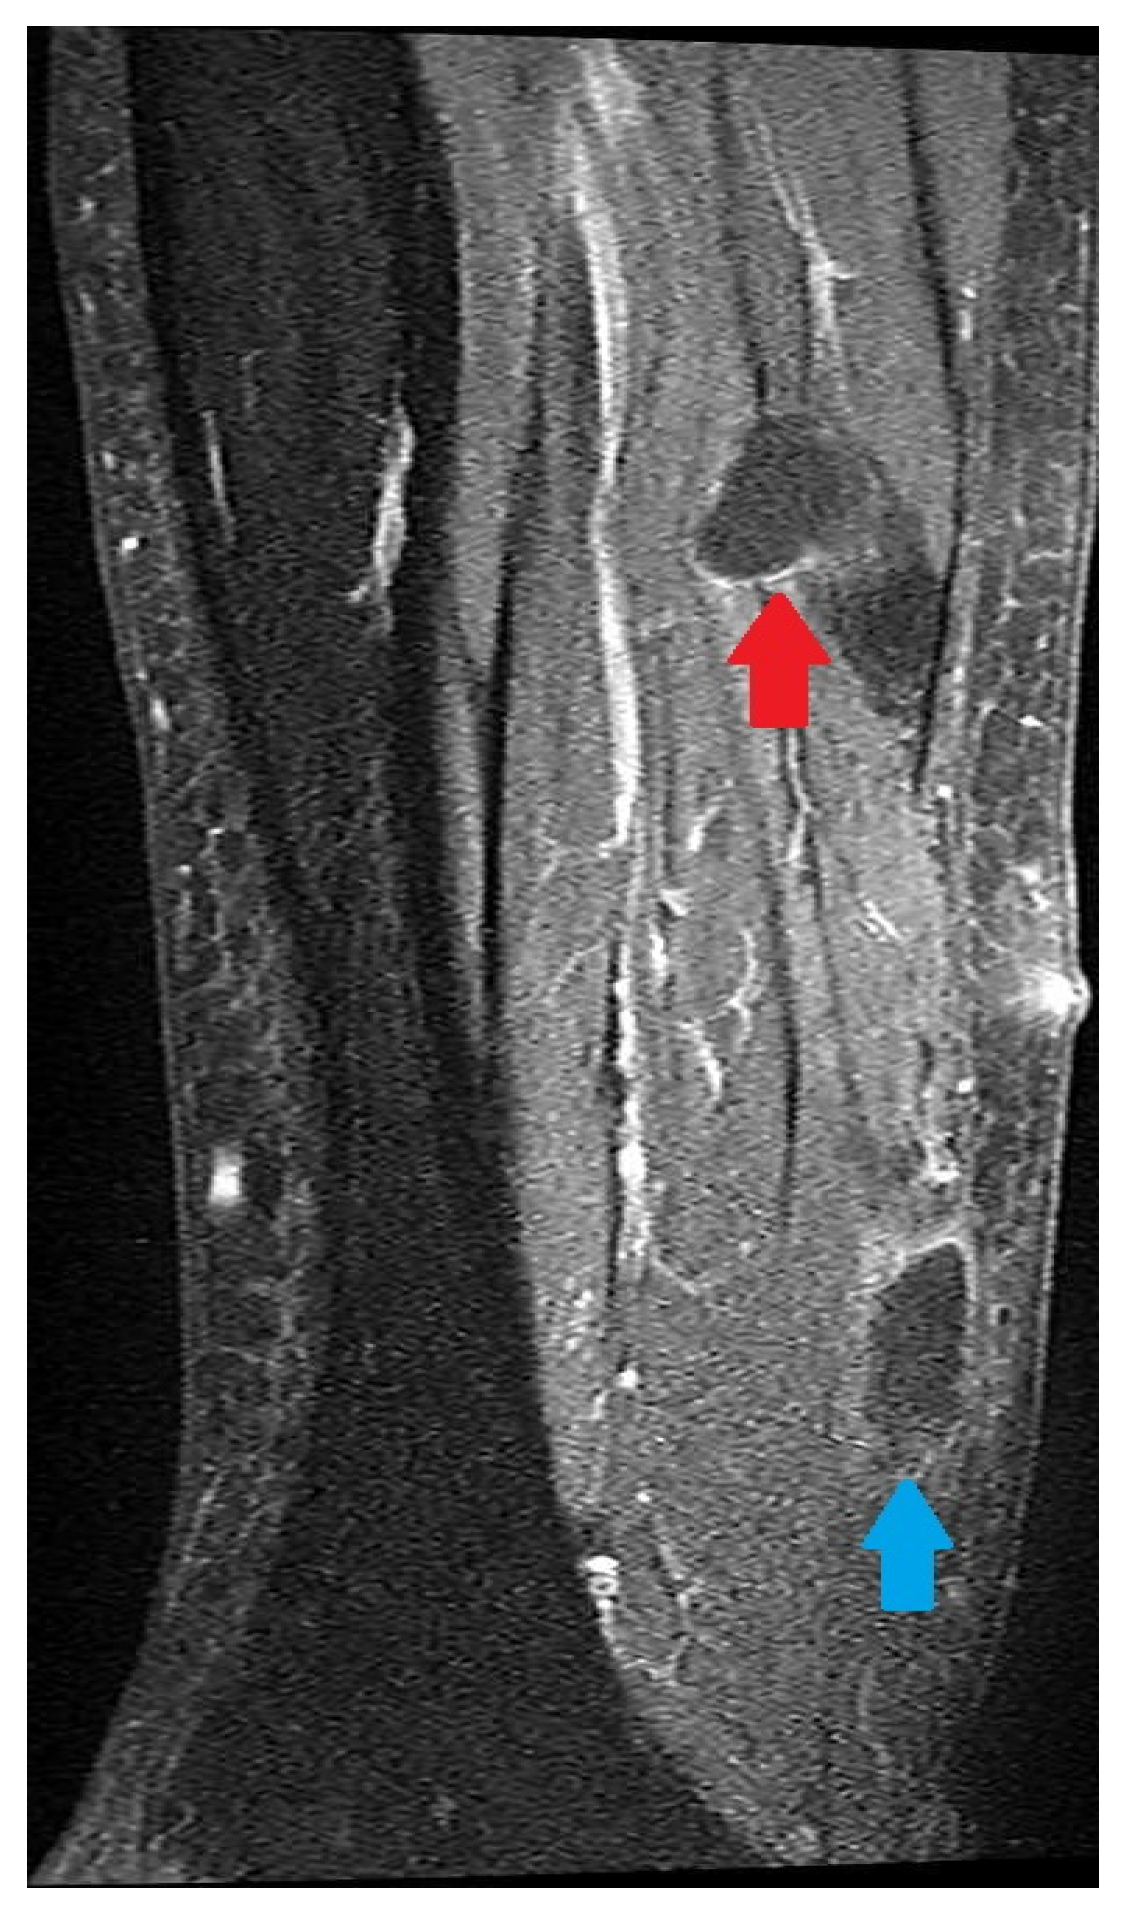

| Radiology | MRI of the head | MSCT of the calf Chest X-ray | MRI of the leg; MSCT of abdomen and pelvis | |||